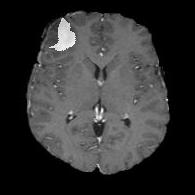

We first introduce a method for connecting the output of a CNN to an ACM, yielding a model for the precise delineation of lesions, to which we refer as Deep Active Lesion Segmentation (DALS) (Figure 4). We then go further to introduce a truly unified framework (Figure 5) that bridges the gap between ACMs and CNNs by leveraging a novel, automatically differentiable level-set ACM with trainable parameters that allows for back-propagation of gradients and can be end-to-end trained along with a backbone CNN from scratch, without any CNN pre-training. The ACM is initialized directly by the CNN and utilizes an energy functional that is locally-tunable by the backbone CNN, through 2D feature maps. Thus, our work overcomes the big hurdle of fully automating the powerful ACM approach to image segmentation. We have applied our proposed framework to the task of building segmentation in aerial images (Figure 6).

Deep Active Lesion Segmentation

[45]: Lesion segmentation is an important problem in computer-assisted diagnosis that remains challenging due to the prevalence of low contrast, irregular boundaries that are unamenable to shape priors. We introduce Deep Active Lesion Segmentation (DALS), a fully automated segmentation framework that leverages the powerful nonlinear feature extraction abilities of FCNs and the precise boundary delineation abilities of ACMs. Our DALS framework benefits from an improved level-set ACM formulation with a per-pixel-parameterized energy functional and a novel multiscale encoder-decoder CNN that learns an initialization probability map along with parameter maps for the ACM. We evaluate our lesion segmentation model on a new Multiorgan Lesion Segmentation (MLS) dataset that contains images of various organs, including brain, liver, and lung, across different imaging modalities—MR and CT. Our results demonstrate favorable performance compared to competing methods, especially for small training datasets. -